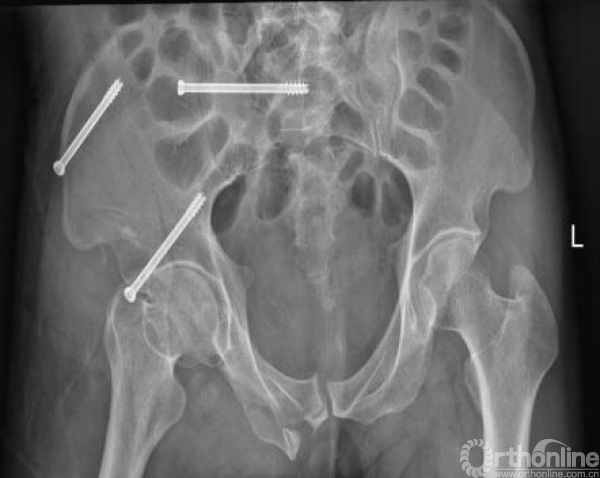

术后复查影像(2017.09.28、2017.10.05)

术后x线(2017.09.17)

骨盆正位、骨盆入口位、骨盆出口位

术后CT影像(2017.10.05)